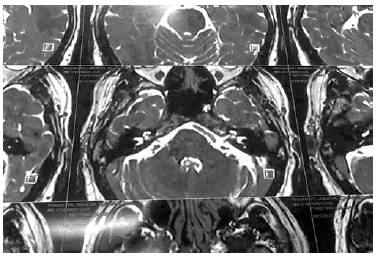

Se realizó estudio de resonancia magnética con gadolinio que evidencia conflicto vascular en relación a dolico arteria cerebeiosa superior, que aparenta contacto con el nervio trigémino (Figura N°1).

Figura N°1.

Resonancia magnética de cerebro, corte axial en fosa posterior, secuencia T2, evidencia arteria cerebeiosa superior izquierda dolicoectásica en proximidad a nervio trigémino en su origen aparente, como factor determinante de conflicto neurovascular.